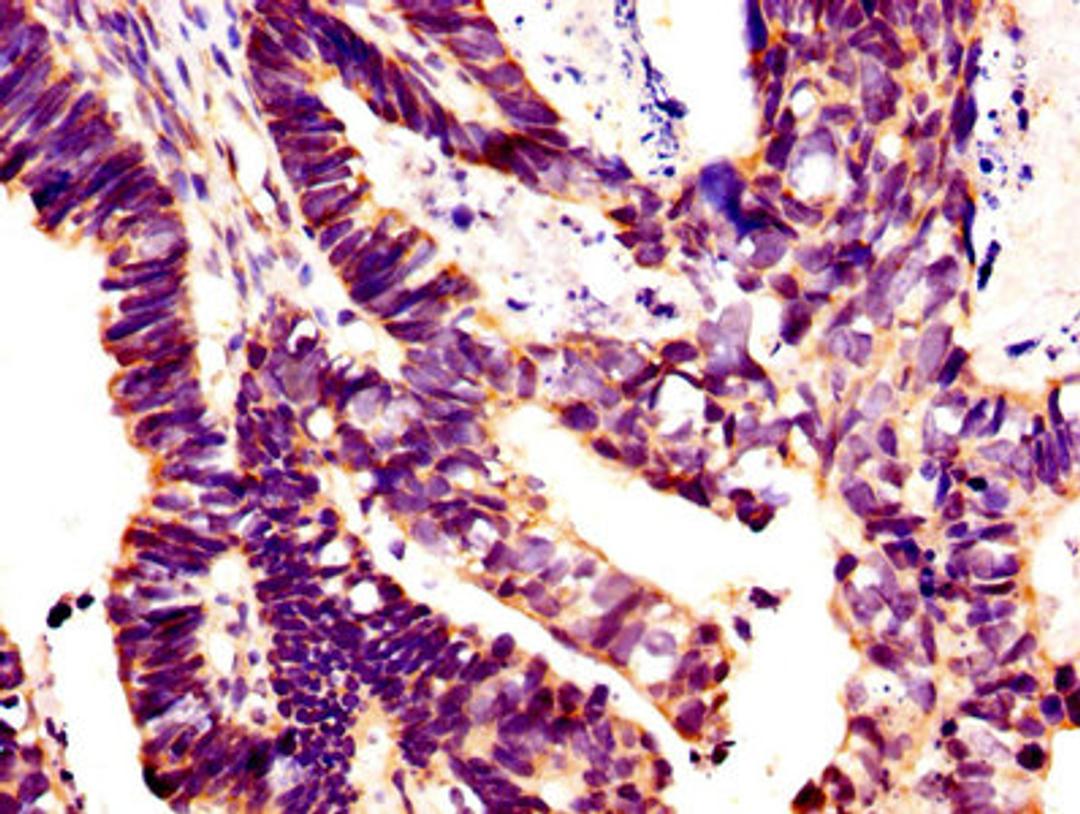

GLI1 Antibody

- Antigen: Recombinant Human Zinc finger protein GLI1 protein (921-1106AA)

- Immunohistochemistry (IHC)